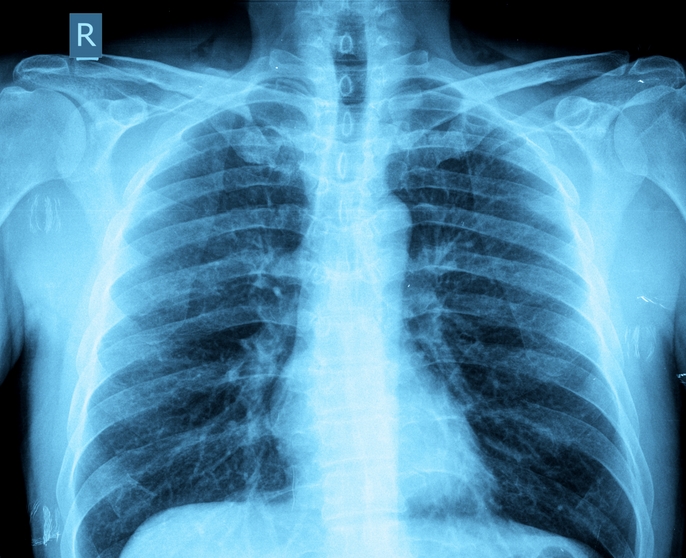

Bebeklerde Akciğerde Enfeksiyon

Bebeklerde Akciğerde Enfeksiyon.